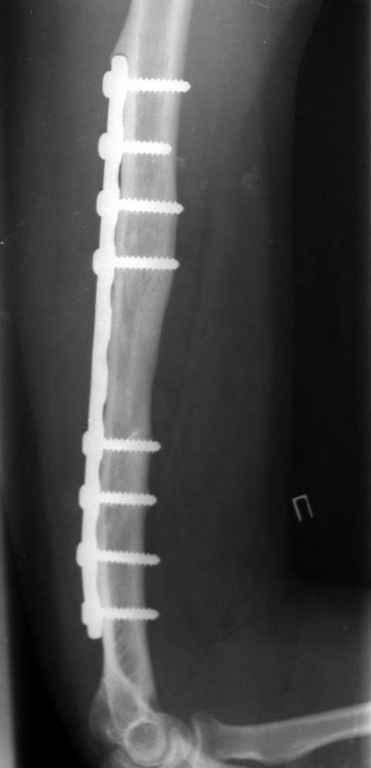

был ли остеосинтез с диастазом - неизвестно, но неадекватность фиксации пластиной достаточно очевидна.

1 пластина тонкая

2 всего 6 шурупов через пластину - для плеча это минимальное требование при свежем переломе

3 проксимальный фрагмент на момент ( или в ходе) второй операции был расколот , о чем свидетельствует наиболее проксимальный lag screw, то есть прокс 3 шурупа через пластину были введены в расколотый фрагмент. Неудивительно, что пластину вырвало

Здравствуйте Владимир! На всех рентгенограммах определяется лизис костной ткани вокруг шурупов, на боковой проекции похоже секвестр, это -- в пользу остеомиелита. Рекомендую: удаление металлоконструкций краевую резекцию концов плечевой кости, ревизию каналов после удаленных шурупов, при наличии признаков остеомиелитических грануляций провести кюретаж. Наложить спице-стержневой АВФ + открытую репозицию отломков. При необходимости проточно- промывное дренирование. Желательно применение Коллапана интраоперационно.